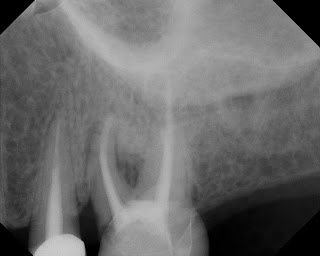

The following case would be typically diagnosed as a root fracture due to the bone loss pattern in the crestal area and into the furcation area as well as a long, narrow 8mm perio pocket on the ML surface. There is however, coronal leakage under the mesial margin which could be a source of re-contamination of the root